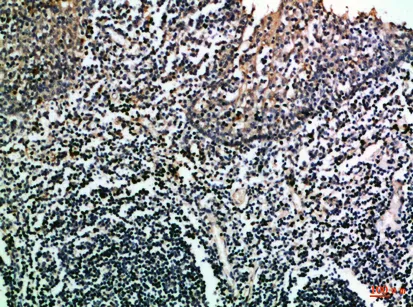

CD275 Rabbit Polyclonal Antibody

Cat: APRab08322